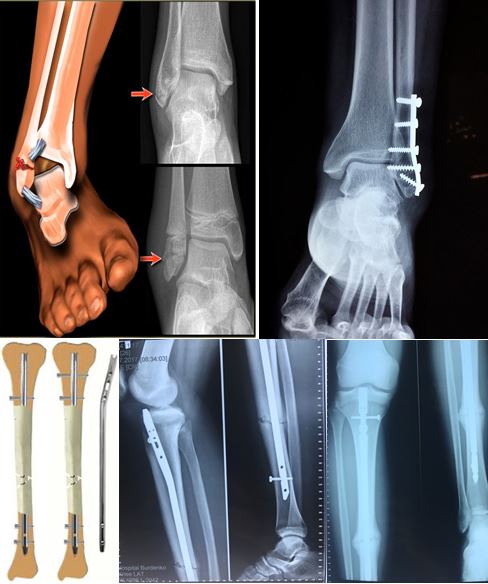

Переломы костей голени

В эту анатомическую область входят: переломы малоберцовой и большеберцовой костей. Они бывают как изолированными, так и комбинированными. Выделяют переломы проксимального и дистального отделов и диафизарные переломы.

В области дистального отдела костей голени следует отдельно выделить переломы наружной и внутренней лодыжек, как наиболее часто встречающиеся переломы. Повреждения в этой области приводят к выраженным функциональным нарушениям, так как гости голени выполняют опорную функцию.

Основным методом лечения этих повреждений является остеосинтез. В зависимости от локализации перелома возможно применение внутреннего остеосинтеза пластинами или интрамедуллярными штифтами.

Одними из первых малоинвазивные методики были разработаны и успешно применены при лечении пострадавших с диафизарными переломами большеберцовой кости. Фиксация отломков большеберцовой кости интрамедуллярным штифтом при локализации переломов в области диафиза – «золотой стандарт» успешно применяемый в ЦТиО.

Ключевым моментом данной операции является не только наличие минимальных по размеру хирургических доступов, но и возможность ранней нагрузки на оперированную ногу. Так интрамедуллярный остеосинтез позволяет вертикализировать пациента уже на вторые сутки после операции, либо значительно облегчает уход за пострадавшим, вынужденно находящимся в лежачем положении.

Также при переломах в данной области в ЦТиО с успехом применяется и накостный остеосинтез, который также представляет собой минимально-инвазивную методику. Во время проведения операции доступ осуществляется из маленьких разрезов, что не нарушает кровоснабжения кости. Это также позволяет сократить сроки восстановительного лечения.

Малоинвазивные методы лечения в умелых руках сотрудников ЦТиО ГВКГ им. Н.Н. Бурденко работают даже там, где, казалось бы, уже всевозможные варианты лечения исчерпаны. Например, при выполнении ортопедических операций по созданию артродеза голеностопного сустава, сросшихся в неправильном положении костей голени после перелома лодыжек.